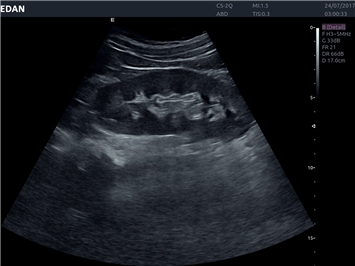

EDAN Acclarix LX4

Расширьте свои представления. Использование усовершенствованной платформой Acclarix система LX4 обеспечивает непревзойденную четкость изображений и интеллектуальный рабочий процесс для всех пользователей, являясь при этом наиболее экономичным решением.

EDAN Acclarix LX4 представляет собой инновационную ультразвуковую систему, построенную на усовершенствованной платформе Acclarix. Сочетание высокого качества визуализации с интеллектуальным рабочим процессом делает эту систему оптимальным выбором для клиник, ценящих эффективность и экономичность.

• Общей визуализации

• Акушерства и гинекологии